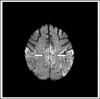

Sporadic Creutzfeldt-Jakob disease is a rare neurodegenerative disorder of unknown etiology that causes rapidly progressive dementia. This disease is uniformly fatal and most patients die within 12 months. Clinical findings include myoclonus, visual disturbances, and cerebellar and pyramidal/extrapyramidal signs in addition to rapidly progressive cognitive and functional impairment. These findings are all non-specific and it is often difficult and challenging to diagnose premortem because of low awareness and clinical suspicion. We present a 66-year-old woman with a 5-month history of rapidly progressive dementia. After a series of extensive diagnostic examinations and continuous follow-up, she was diagnosed with probable sporadic Creutzfeldt-Jakob disease based on Centers for Disease Control and Prevention (CDC) criteria, with key findings of rapidly progressive dementia, blurry vision, extrapyramidal signs (cogwheel rigidity), and abnormal hyperintensity signals on diffusion-weighted MRI. Her symptoms progressively worsened and she died 7 months after the onset. The postmortem brain autopsy demonstrated the presence of abnormal protease-resistant prion protein by Western Blot analysis. A literature review was performed on differential diagnoses that present with rapidly progressive dementia and thereby mimic sporadic Creutzfeldt-Jakob disease. These include Alzheimer's disease, dementia with Lewy Bodies, frontotemporal dementia, meningoencephalitis, corticobasal degeneration, progressive supranuclear palsy, CADASIL, and paraneoplastic encephalomyelitis.